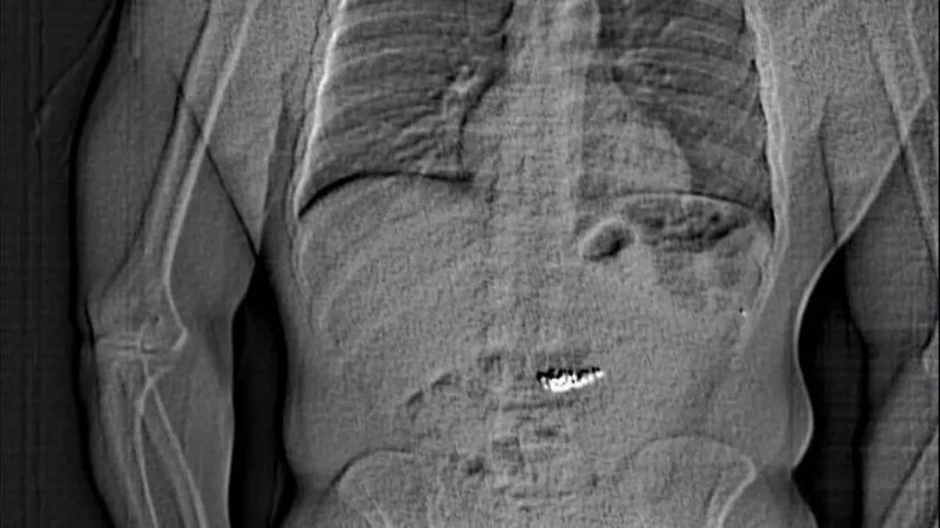

Policija je objavila tudi rentgenski posnetek Gilderjevega želodca, kjer so uhani dobro vidni.

12. marca so se uhani izločili iz njegovega telesa. Bili so vrnjeni v prodajalno, kjer so potrdili istovetnost in jih očistili.